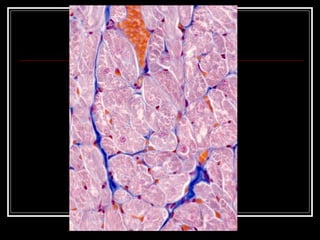

TEJ.MUSCULAR CARDIACO CELULAS RAMIFICADAS  DISCOS INTERCALARES NUCLEO CENTRAL SARCOPLASMA MAS ABUNDANTE MAS MITOCONDRIAS  CARECE CAPACIDAD REGENERATIVA

TEJ.MUSCULAR CARDIACO CELULASRAMIFICADAS DISCOS INTERCALARES NUCLEO CENTRAL SARCOPLASMA MAS ABUNDANTE MAS MITOCONDRIAS CARECE CAPACIDAD REGENERATIVA